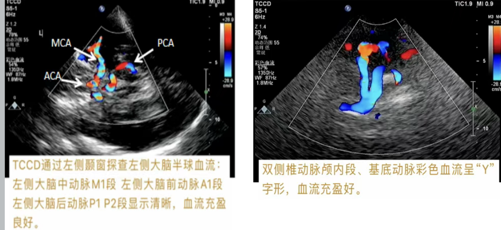

颈-脑联合超声通过颈部血管超声+经颅多普勒超声(TCCD),同步评估颅内外及颈部15条动脉,精准定位颈部斑块、血管狭窄及血流异常,避免漏诊。